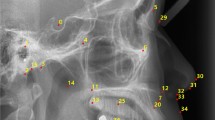

Cephalometric tracing on synthesized images

Cephalometric tracing by identifying landmarks is important step for orthodontic diagnosis and treatment planning. To use synthesized image on augmentation purposes for improving deep learning models and other clinical situations, landmarks containing clinical information should be identified accurately. To verify the position recognition rate of landmarks, a total of 42 landmarks were traced by two orthodontists (J. Park and S. E. Jang) on the 50 synthesized images used for SNR measurement. The orthodontists knew that the cephalometric images were synthesized. They traced the landmarks according to their anatomical definitions. A cephalometric image with the landmark positions is shown in Supplementary Appendix Fig. S1 and their names are shown in Supplementary Appendix Table S1. We compared each point of traced landmark differences between the two readers. Then, the average difference was calculated and different landmark points were discussed.

The landmark-position differences between the two orthodontists are shown in Table 2. The average difference was 2.08 ± 1.02 mm. The landmark position with the largest difference was the occlusal plane point (5.95 ± 2.42 mm).

Most of the landmark points identified by the orthodontists had no significant differences between them. Because the landmark positions are identified by the relative positions of anatomical structures, the differences were evaluated by dividing them into the horizontal and vertical axes of the Cartesian plane. Using this metric, 29 landmark points out of 42 showed less than a 2 mm difference in the Cartesian plane. For point A at the maxilla and point B at the mandible regions, the differences in the horizontal direction were smaller than those in the vertical direction. These points were mainly used to evaluate the anterior–posterior relationship. In contrast, the anterior and posterior nasal spine points, which are important for identifying the palatal plane, had smaller differences in the vertical direction than in the horizontal direction. This indicates that the difference is not random but occurs systematically depending on the positional definitions of the landmarks.

The landmark with the largest difference between the orthodontists’ definitions was the occlusal-plane point (see red box in Fig. 5). The difference in the point’s horizontal direction was 5.87 ± 2.43 mm and that in the vertical direction was 0.76 ± 0.54 mm. This point is located at the center of the occlusal plane, which is defined by the position of the first premolar and thus can be identified along the horizontal direction. In the synthesized image, although the structure of the first premolar was unclear and had artifacts, the occlusal plane point was not affected in the vertical direction. Consequently, the occlusal plane point had large horizontal differences between the orthodontists' definitions; however, this artifact did not affect the slope of the occlusal plane.